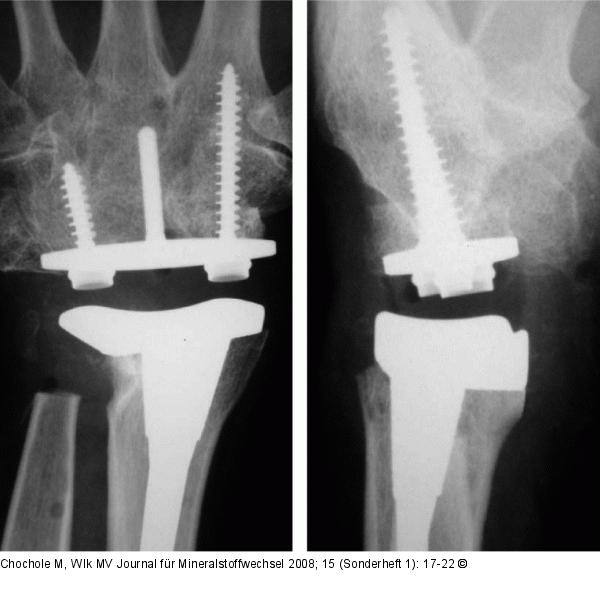

Abbildung 2: Prothese Postoperative Röntgenkontrolle nach Universal®-Handgelenksendoprothese Integra. |

Postoperative Röntgenkontrolle nach Universal®-Handgelenksendoprothese Integra. |